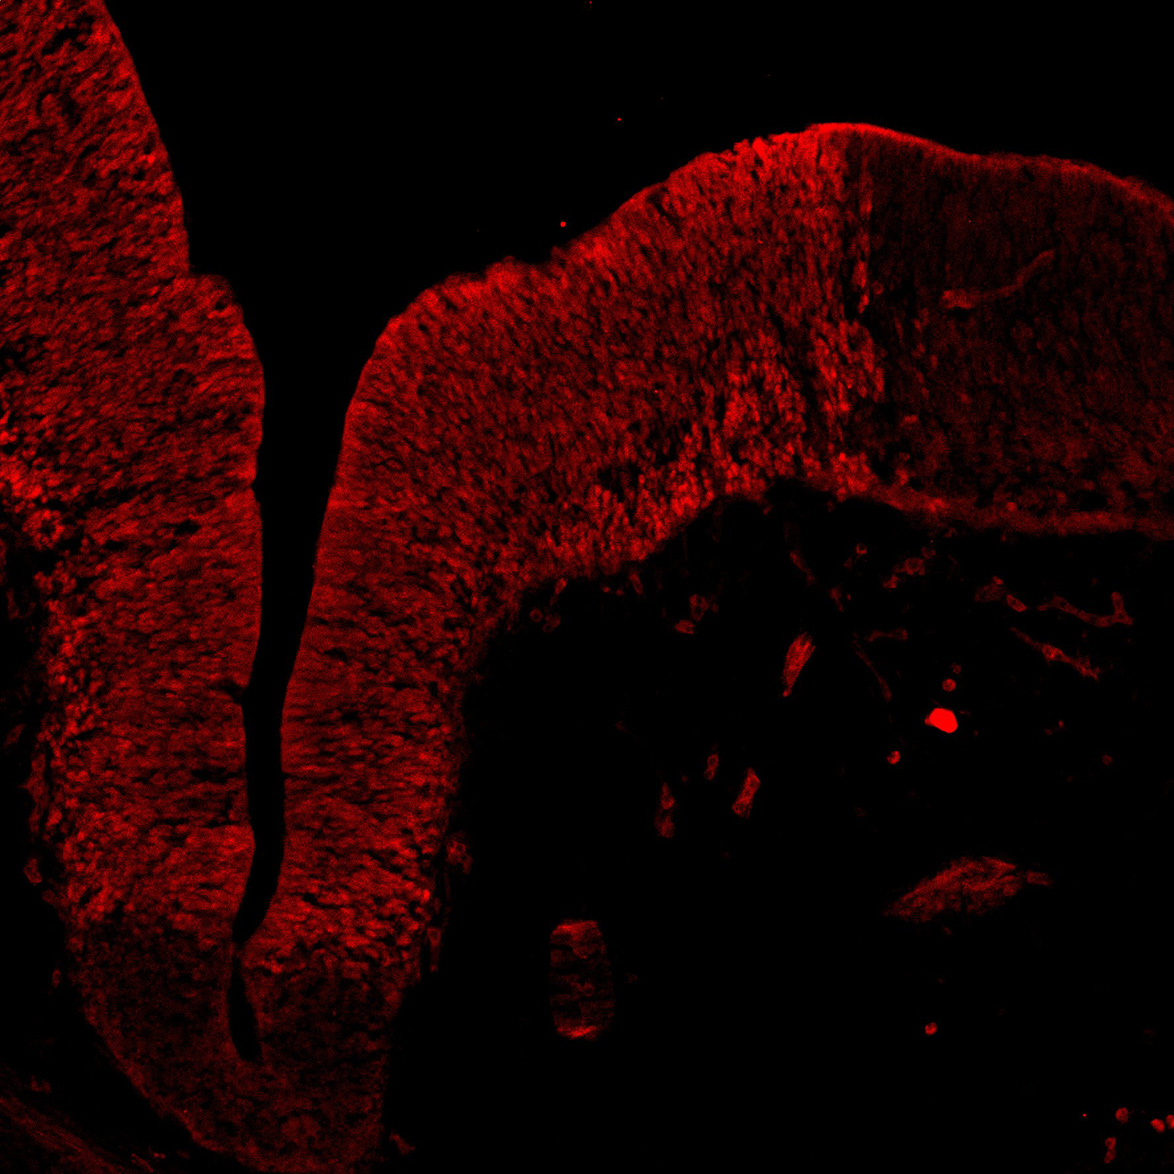

TH

7PCW human midbrain

11PCW human midbrain

13PCW human midbrain

15PCW human midbrain

17PCW human midbrain

19PCW human midbrain

22PCW human midbrain